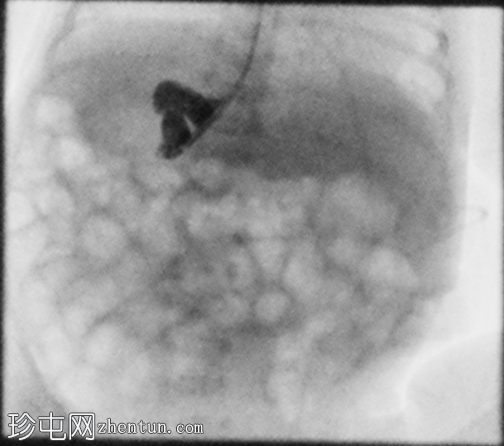

定位片显示肠道气体分布无梗阻,经食管插管终止于右上腹。

胃位于右上腹。观察到轻度中段食管反流。造影剂在近端十二指肠的延迟通过量极少,这属于异常情况。

延迟正位和侧位X线片显示肠内容物通过时间极短。